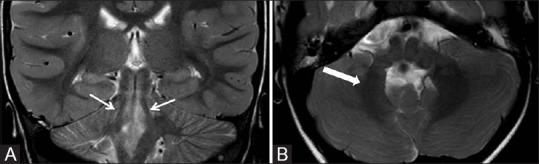

Malformations involving the brainstem are very rare and present with a varied spectrum of clinical symptoms due to multiple cranial nerve palsies and pyramidal tract involvement. Of these, pontine tegmental cap dysplasia is a very unusual malformation, characterized by ventral pons hypoplasia and an ectopic dorsal band of tissue, projecting into the fourth ventricle, from dorsal pontine tegmentum. A 4-year-old male child, presenting with left facial nerve palsy, revealed hypoplastic ventral pons and an ectopic structure on magnetic resonance imaging (MRI). The ectopic structure was isointense to pons, arose from the left side of dorsal pontine tegmentum, at pontomedullary junction and protruded into the fourth ventricle, impinging upon the left seventh and eighth cranial nerves. Diffusion tensor imaging (DTI) depicted abnormal white matter tracts in ectopic tissue with absent transverse pontine fibres and abnormal middle and superior cerebellar peduncles. The typical MRI appearance, coupled with DTI, helped us reach an accurate diagnosis of pontine tegmental cap dysplasia, in a setting of neurological dysfunction.

累及脑干的畸形非常罕见,由于多组颅神经麻痹和锥体束受累,会出现各种各样的临床症状。其中,脑桥被盖帽发育异常是一种非常罕见的畸形,其特征是脑桥腹侧发育不全,以及从脑桥背侧被盖向第四脑室突出的异位组织带。一名4岁男童,表现为左侧面神经麻痹,磁共振成像(MRI)显示脑桥腹侧发育不全和一个异位结构。该异位结构与脑桥等信号,起源于脑桥延髓交界处脑桥背侧被盖左侧,突入第四脑室,压迫左侧第七和第八颅神经。弥散张量成像(DTI)显示异位组织中的白质束异常,脑桥横纤维缺如,小脑上脚和中脚异常。典型的MRI表现,结合DTI,有助于我们在神经功能障碍的情况下准确诊断脑桥被盖帽发育异常。